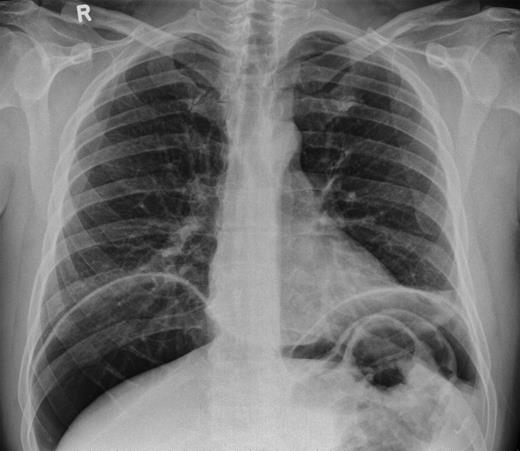

He was taken for urgent laparotomy to evacuate the free gas and aid diagnosis. The bowel was extensively examined and no evidence of perforation was found. The abdominal wall was closed and he returned to the ward. Subsequent X-rays showed that the pneumoperitoneum had resolved. Post-operatively his CRP level was 226 and he went into ileus requiring nasogastric tube placement (Fig. 3). With recurrence of normal bowel activity and with settling of his symptoms, he was discharged.